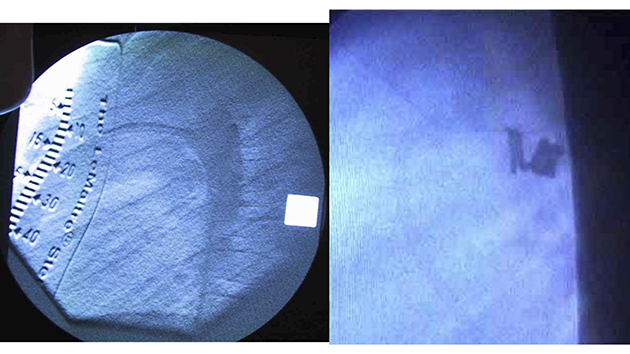

このころ、モンゴル国立母子保健センターには心臓カテーテル血管造影室がなかったので、第1回から第3回渡航の前半は、手術室の窓に暗幕を張り、ポータブルの透視装置を持ち込んで臨時カテ室にしました。

撮影して画像を残すことができなかったので、皆で覗き込んで、一瞬の画像で判断しました。

第1回渡航のカテ6番目、PDA閉鎖としては5番目症例の実際の画像です。

1才7カ月、体重10kgの女児のPDAを、8mm-8cmと6mm-8cmの052コイル2個で閉鎖しました。